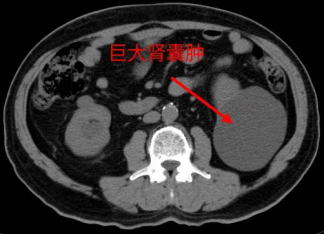

我院外科成功开展双侧巨大肾囊肿超声引导下穿刺固化引流术

B超显示,张大爷左肾囊肿最大直径12cm,右肾囊肿最大8cm。我院外科团队和功能科超声团队会诊后,考虑到病人71岁的年龄和患有心肺多种基础病,共同制定了“超声引导下肾囊肿穿刺固化引流术”治疗方案。